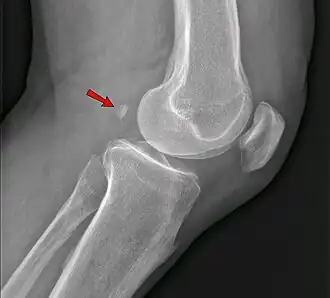

Genou

Un os surnuméraire peut provoquer un diagnostic radiographique érroné de fracture[19].